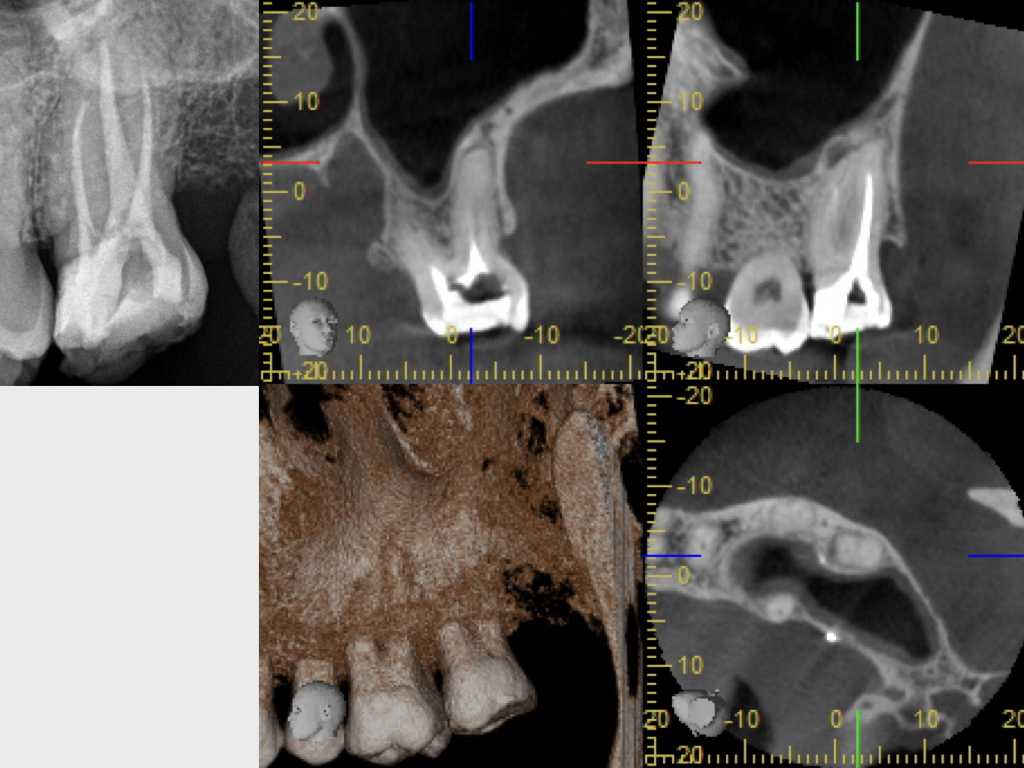

WSPick1.003

Pick, Pick (1)